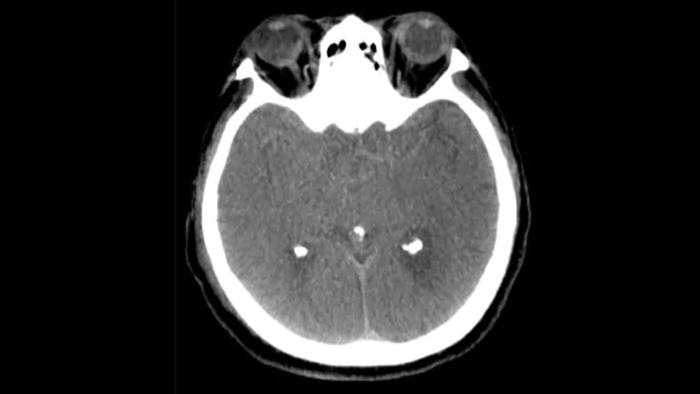

КТ-подобная визуализация

SmartCT Soft Tissue выполняет КТ-подобную визуализацию мягких тканей и дополняет диагностику инсульта тремя способами. Технология бесконтрастного сканирования помогает выявить ишемические изменения на ранних стадиях. Сканирование ранней фазы помогает определить проксимальную окклюзию. Сканирование поздней фазы с усилением контраста направлено на обнаружение коллатералей.

Перипроцедурная проверка кровотечений

SmartCT Мягких тканей

Используйте изображения, полученные с помощью SmartCT (КТ-подобные), с решением Neurovascular Suite, чтобы убедиться в успешности лечения и осуществить проверку на наличие кровотечений.